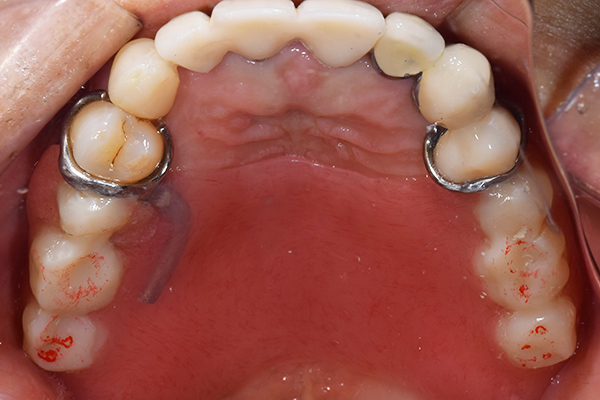

8.患者様のお口に入れて修正

この写真は、実際にお口の中にいれてみて、噛み合わせのチェックを行い、調整したものになります。 上下の入れ歯で青い点、赤い点がはっきりあり、これはしっかり奥歯で噛めるというサインになります。 また、入れ歯自体の大きさや、違和感が強くないか、お顔と調和しているか、唇との関係などをみていきます。もし、ここで大きな修正が発生する場合はもう一度お時間をもらって次回再度確認させて頂きます。 これで修正が終わったら、その模型を技工所に送り、入れ歯を完成させてもらいます。

ケース4

(アタッチメントを用いた部分入れ歯)

右上のインプラント周囲炎で、その部分が痛いという患者様でした。 また奥歯で噛むことが難しかったため、前歯を使用することが多くなり、 前歯が前よりも前に出てきていることも気になっていらっしゃいました。

インプラント部以外にも歯周病が進行していましたので、歯周病の治療を行いました。 残念ながらインプラントと、1本の歯が残せなかったため抜歯を行いました。 その後、前歯の出っ張りを修正することと入れ歯の安定を図るため、残っている歯を全てかぶせ物にしていくことになりました。 写真中央は抜歯後に入れた治療用の入れ歯になります。 抜歯後歯ぐきが安定しましたら、入れ歯とかぶせ物の型取りを行いました。

噛み合わせチェックでしっかり奥歯で噛めるようにし、 歯を並べます。 その後、それに合わせて前歯を作っていきます。

最終的な入れ歯用の型取りをします。 シリコンで精密に型取りができました。

こちらが完成したかぶせ物と入れ歯です。かぶせ物にはアタッチメントをつけて金属のバネが見えない構造になっています。 入れ歯自体も金属を使用して、極力違和感がでないように、薄く作成しました。

お口の中に入れた状態です。 非常に見た目もよい出来となりました。 バネがみえないと見栄えが全然ちがいます。

年齢 70代・女性

主訴 奥歯のインプラントが痛い。

前歯がでてきた。

治療期間 6ヶ月

治療費 .メタルボンドクラウン7本:770,000円

.アタッチメント2個:220,000円

.義歯:550,000円

治療方針 ゆれてきたインプラントを抜去した後、歯周病の治療と、予後不良の歯を抜歯して、義歯を作成します。

抜歯後は治療用の入れ歯を作成し、ものが噛める様にします。

また前歯は、被せものをすることにしました。

治療内容 右上のボーンアンカードブリッジ(インプラントのブリッジ)部分がインプラント周囲炎になり、ぐらぐら揺れてきました。

そのため、インプラントを抜去した後、歯周病の治療と、予後不良の歯を抜歯して、義歯を作成していきました。

見た目が入れ歯とわからない様に針金のない、アタッチメントを使用した入れ歯を作成することにしました。

抜歯後は奥歯でものが噛める様に治療用の入れ歯を作成しました。

また前歯はフレアアウト(奥歯で噛めなくて前歯で噛む様になって、前歯が前に出てくる現象)していたため、患者さんの希望でかぶせ物をすることにしました。

特記事項 歯やインプラントを抜いた後は、2〜3ヶ月歯ぐきの回復を待ってから入れ歯を作るため、待機期間があります。その間、治療用の入れ歯を調整しながら使います。かぶせものをした後は歯がしみたり、場合によっては神経を抜く処置が必要になることもあります。